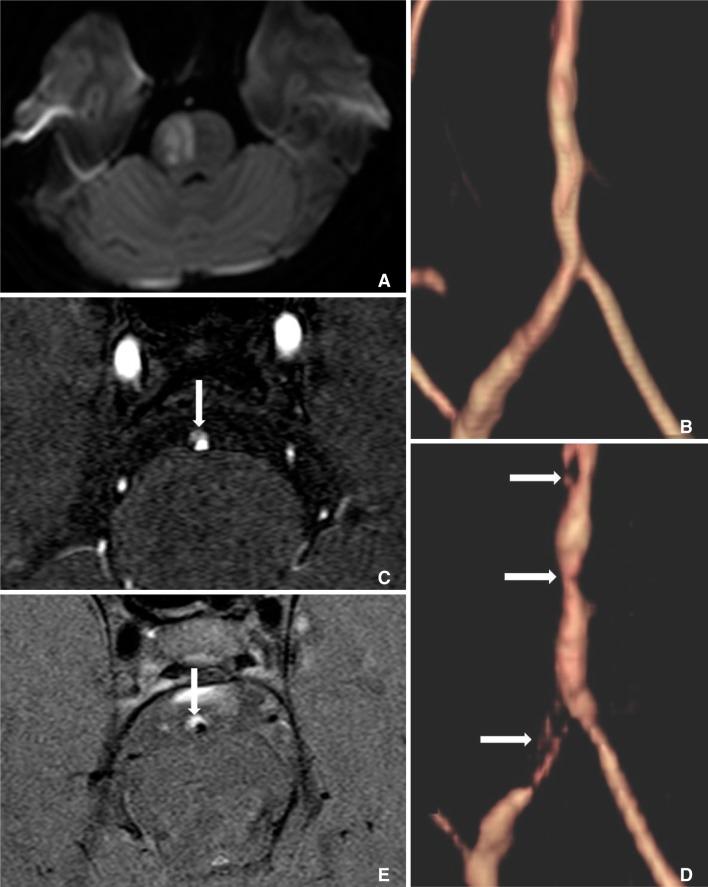

Spontaneous intracranial vertebrobasilar dissection can manifest with various clinical symptoms, including subarachnoid hemorrhage or ischemic symptoms from impaired posterior circulation. A 29-year-old woman came to our emergency department with a sudden onset of left sided mild motor weakness and headache. Initial magnetic resonance imaging (MRI) showed mild luminal irregularities in the vertebrobasilar arteries with an eccentric periluminal hematoma. Follow-up MRI obtained 3 days later showed a progression of vertebrobasilar dissection to multifocal stenoses with an increased intramural hematoma.

自发性颅内椎基底动脉夹层可表现为多种临床症状,包括蛛网膜下腔出血或后循环受损导致的缺血症状。一名29岁女性因突然出现左侧轻度运动无力和头痛前来我院急诊科就诊。初始磁共振成像(MRI)显示椎基底动脉管腔轻度不规则,伴有偏心性管周血肿。3天后进行的随访MRI显示椎基底动脉夹层进展为多灶性狭窄,壁内血肿增大。